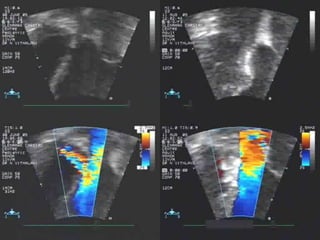

Echocardiographic delineation of pmVSD

Echocardiographic delineation of various VSDs

Not suitable for

Device closure

based

on location

assessed

by echo

Which VSD is suitable for device closure

Suitable device for defect? rims?

 Not suitable based on

echocardiographic assessment:

Defect diameter too large (no

appropriate device available)

Rims too small or even absent (e.g. rim

to aortic valve)

Exclusion criteria for VSD closure

Overriding Aorta (TOF) Aortic cusp prolapse

(= malalignment VSD)

prolapse of aortic cusp

Supracristal VSD Inlet VSD

Decision for suitability of VSD closure can be made by echo!